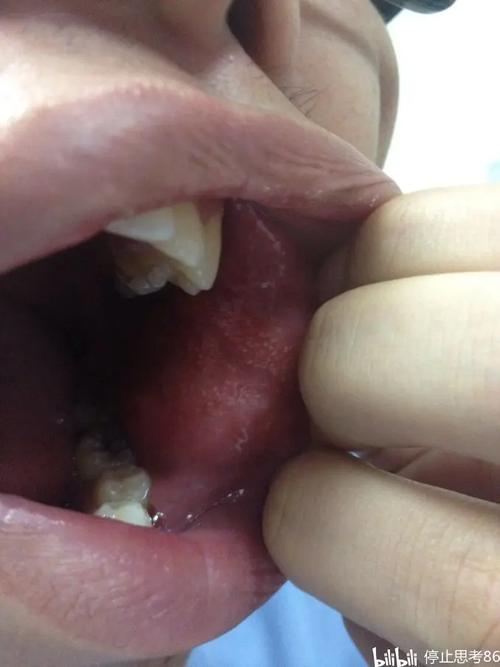

晚期最危险的并发症:癌变

这是OSF晚期最令人担忧的后果。

- 高风险性: 口腔黏膜下纤维化被世界卫生组织列为癌前状态,长期的炎症刺激和细胞代谢异常,使得黏膜上皮细胞发生癌变的几率极高。

- 癌变率: 癌变率报告不一,但普遍认为在 7% - 13% 之间,有些研究甚至更高。

- 不易早期发现: 癌变区域(通常是白色斑块,即“白斑”)与OSF本身的白色病变难以区分,容易被忽视。

- 恶性程度高: 一旦发展为鳞状细胞癌,其侵袭性强,生长迅速,预后较差,治疗难度大。

- 在原有的白色或棕黄色基础上,出现局部红斑、糜烂、溃疡长期不愈。

- 病变区域突然增厚、硬结。

- 自发性出血或轻微刺激后出血。

- 出现不明原因的疼痛或牙齿松动。